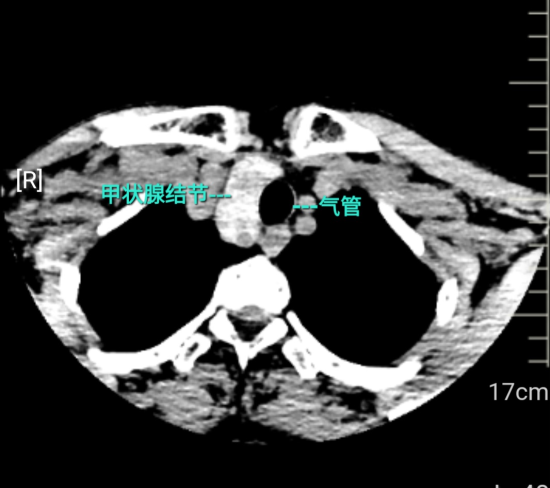

中新网黑龙江新闻12月16日电(刘璐)58岁的张女士(化名)近半年来总感觉颈部有隐隐的束缚感,仿佛衣领过紧,睡觉时平躺偶尔会出现呼吸不畅,甚至能听到自己轻微的“喉鸣”声。起初她并未在意,直到一次常规体检的超声检查:甲状腺右侧叶长有一个直径近5厘米的巨大囊实性混合结节,且超声明确指出,该肿物已延伸至胸骨后方,并压迫气管,导致气管向左侧偏移。

为保证患者颈部美观,李广恩教授选择沿颈部自然皮纹作一弧形切口。术中见右侧甲状腺明显增大,肿物向下生长进入胸骨后上纵隔,该区域空间狭小,密布气管、食管、大血管及重要神经。手术采用精细化被膜解剖技术,在清晰视野下沿自然间隙分离,最大程度保护喉返神经和甲状旁腺,同时使用神经监测仪为神经安全提供额外保障。凭借丰富经验,李教授在不劈开胸骨的情况下,将胸骨后肿物完整游离并取出,解除了其对气管的“箍圈”式压迫。肿物切除后,可见原本被挤压左移的气管立即向中线回弹,受压状态瞬间解除。术中出血仅5ml,喉返神经监测信号良好。